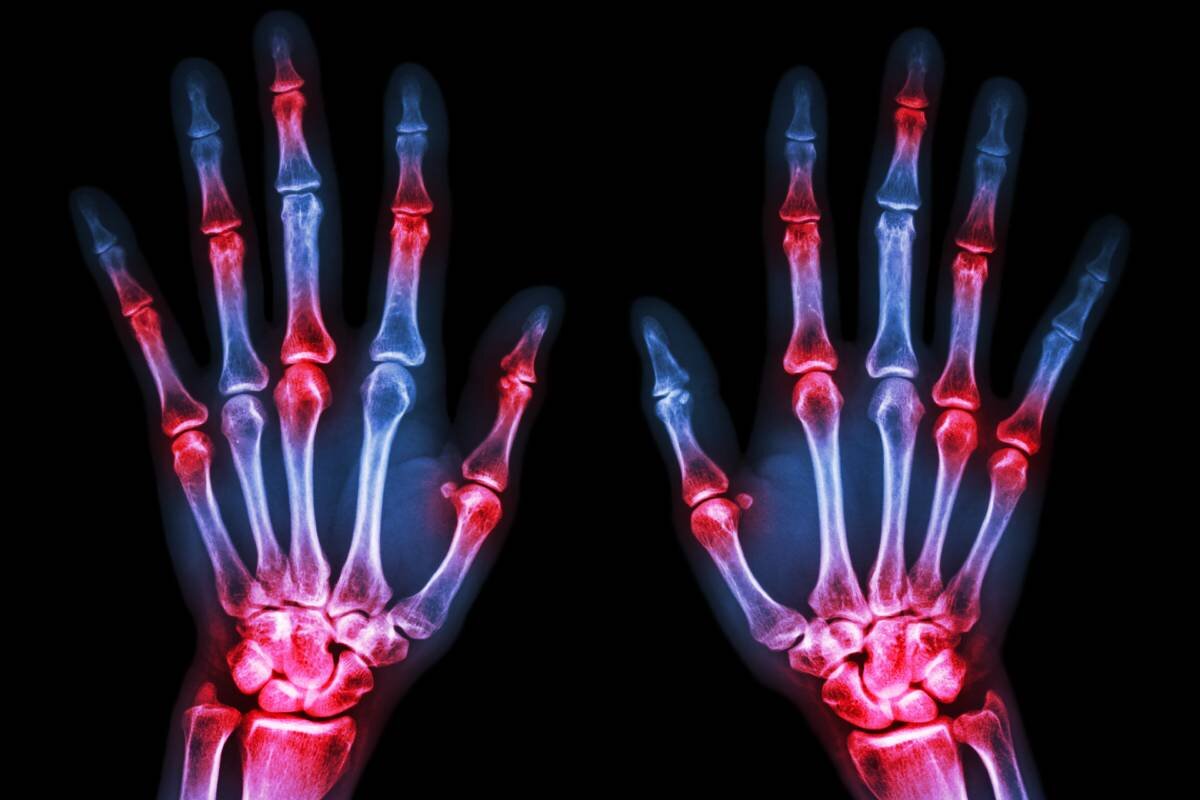

Синдром возрастной кисти, иначе известный как дегенеративные изменения в руках, представляет собой состояние, при котором возрастные или патологические изменения в организме сказываются на функциях кисти. Эти изменения проявляются разнообразно, включая внешние признаки, такие как узловатые пальцы, а также ухудшение подвижности и тактильной чувствительности рук. Доктор медицинских наук Кирилл Прощаев объяснил, что каждое движение кисти зависит от слаженной работы нервной системы, и даже небольшие нарушения в этом балансе могут привести к потере контроля над кистью или снижению ее чувствительности. Он также отметил, что основные причины старения кисти кроются в общих процессах старения тканей конечности и различных заболеваниях. Наиболее распространенной проблемой, связанной с этим синдромом, является существенное снижение подвижности и гибкости суставов кисти, что часто наблюдается у людей пожилого возраста. Это связано как с возрастными изменениями в самих суставах, так и с атрофией ки